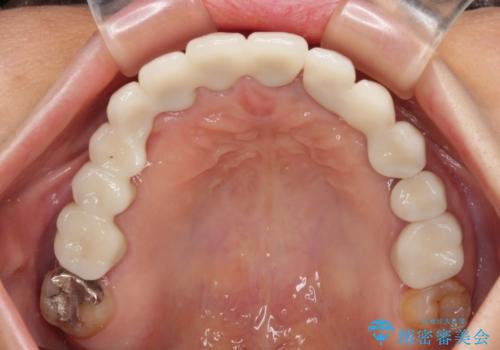

上顎はほぼ全ての歯をセラミッククラウンにて補綴治療を行う必要があるため、気になるデコボコや深い咬み合わせを改善するために下顎と上顎の臼歯部の矯正治療を行うこととしました。

過蓋咬合(下顎前歯が隠れてしまうほどの深い咬み合わせ)のため、スムーズに歯が動かず矯正治療に時間がかかりましたが、無事に仕上げることができました。

セラミック治療の注意事項(リスク・副作用など)

- 天然歯を削ります

- 硬い素材は天然歯を傷つけてしまう場合があります

- かみ合わせや歯ぎしりが強すぎる方はセラミックが割れてしまう可能性があります